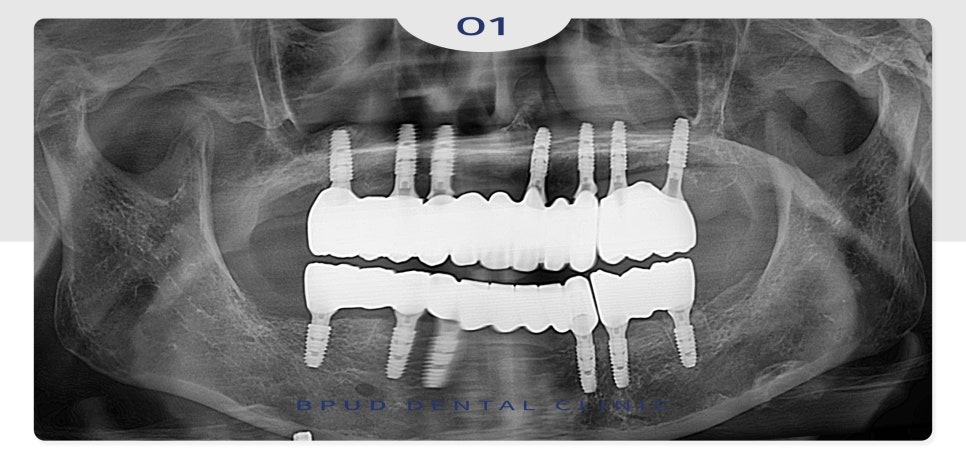

24.01.04

이후 인공치근과 잇몸뼈가 충분히

융합될 수 있도록 4~5개월의 기간을

기다려준 후 순차적으로 보철을 완성하였습니다.

눈에 보이는 잇몸뼈의 양이 적거나

골밀도가 약한 경우, 치아 상실 후 오랜 기간

방치되었다면 잇몸뼈의 양이 소실되기 때문에

뼈이식을 고려해 보아야 하는데요.